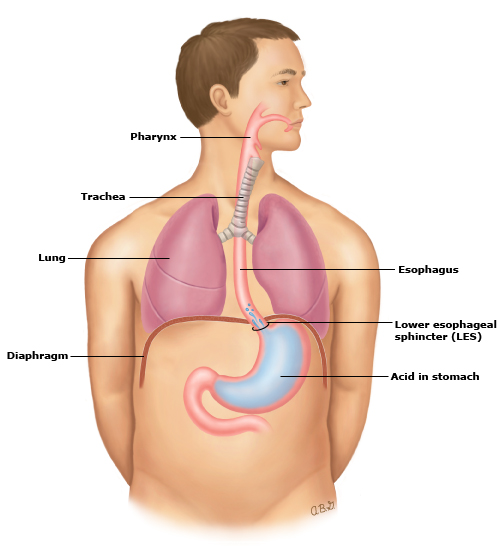

Анатомия желудка и сердца: визуализация и изучение

Раздел: Фотопанорама